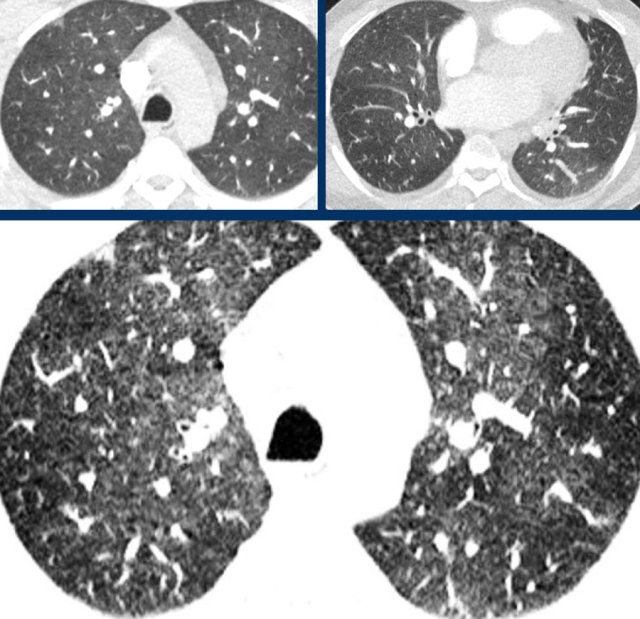

The images are all of patients with proven COVID-19 infection.

The CT's were classified as CO-RADS 5, which indicates a very high probability of COVID-19.